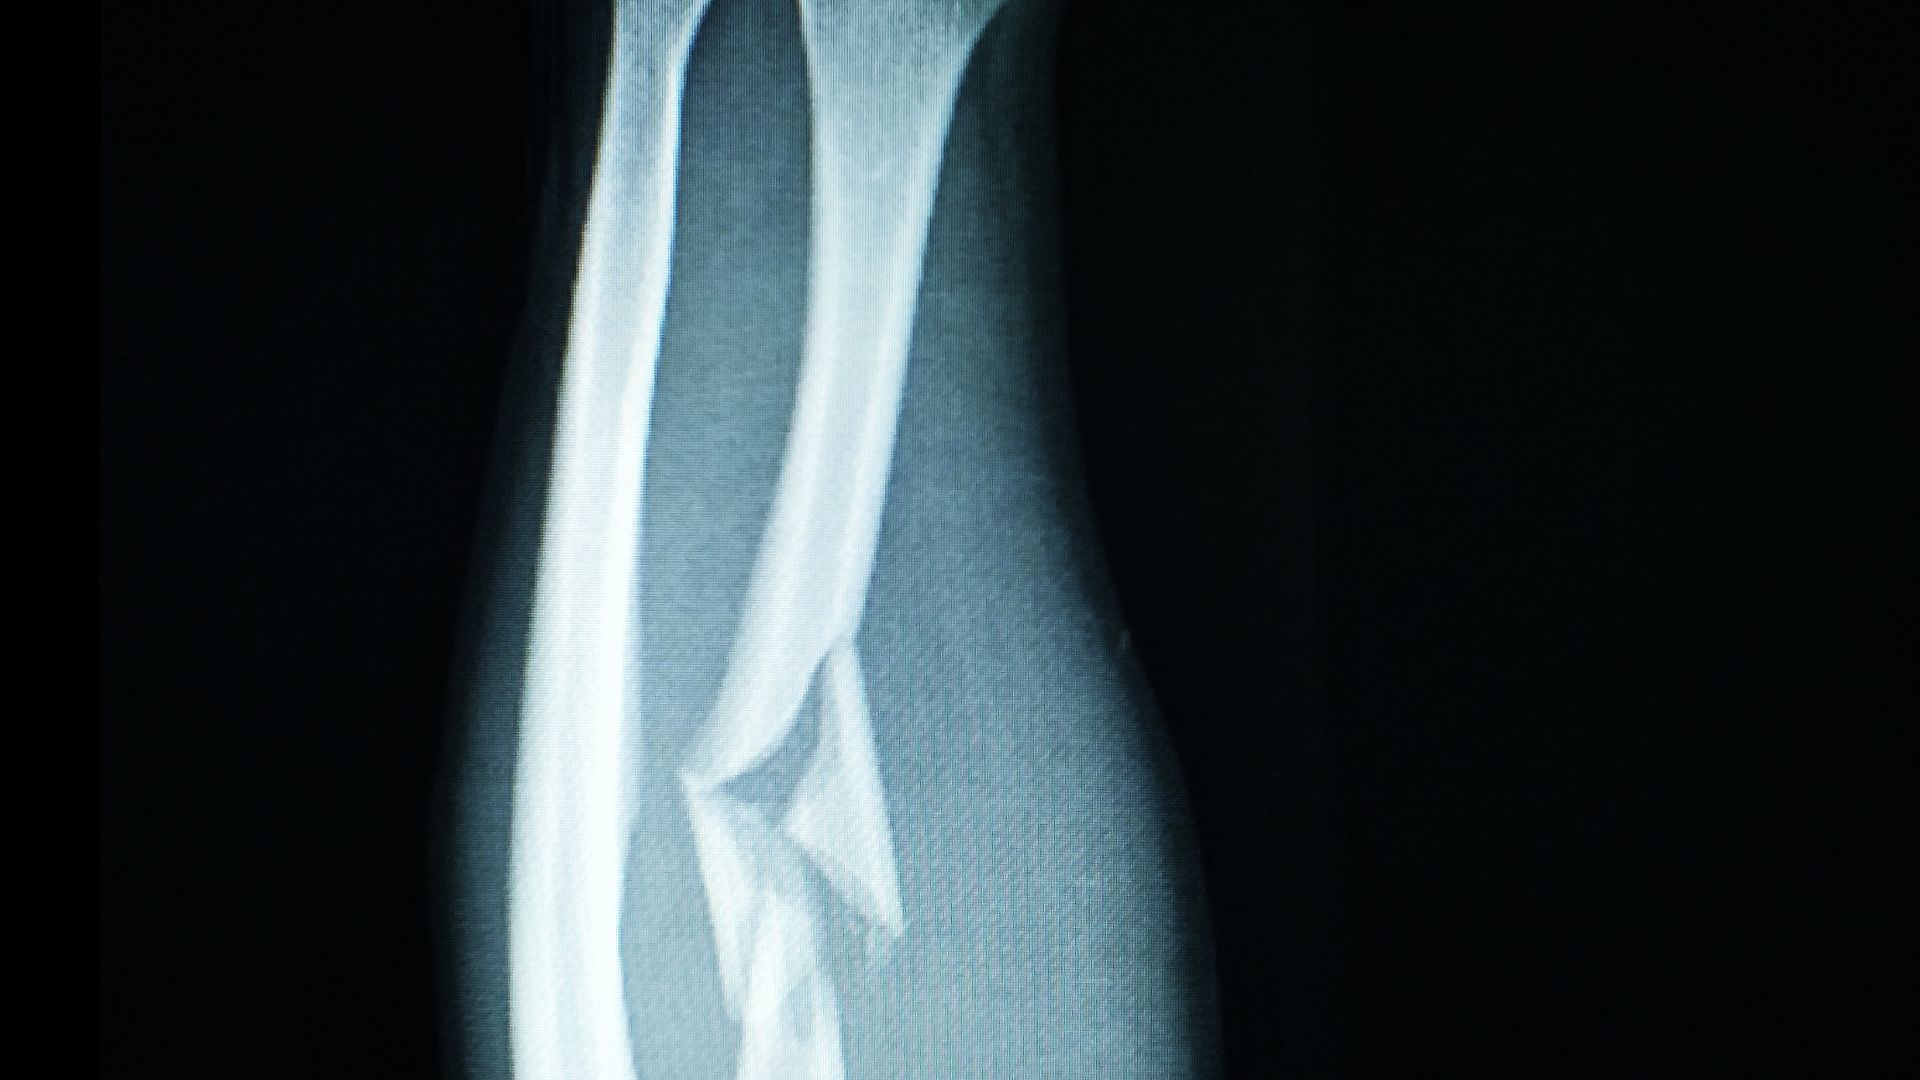

Gãy xương cẳng tay là tình trạng tổn thương xương xảy ra tại đoạn tay nằm giữa khuỷu tay và cổ tay. Về mặt giải phẫu, cẳng tay gồm hai xương chạy song song là xương quay và xương trụ. Khi có lực tác động đủ mạnh, một trong hai xương hoặc cả hai xương này có thể bị nứt, gãy ngang, gãy chéo hoặc gãy vụn.

Bác sĩ sẽ thăm khám lâm sàng kết hợp với chẩn đoán hình ảnh để xác định tình trạng xương. Chụp X-quang là phương pháp phổ biến giúp đánh giá vị trí gãy, dạng gãy và mức độ di lệch. Trong những trường hợp phức tạp, các phương tiện chẩn đoán khác có thể được sử dụng để đánh giá tổn thương phần mềm và cấu trúc xung quanh.